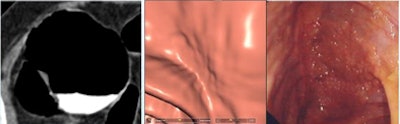

Two lesions were detected only by CAD and were not reported by the radiologists as flat due to low conspicuity. Two lesions with heights < 1 mm weren't seen at CTC but were detected at conventional colonoscopy.

| Two lesions showing a typical cigarlike appearance were detected only by CAD and were not reported by the radiologists as flat due to low conspicuity. Left to right: 2D image, 3D endoscopic view, colonoscopy view. |